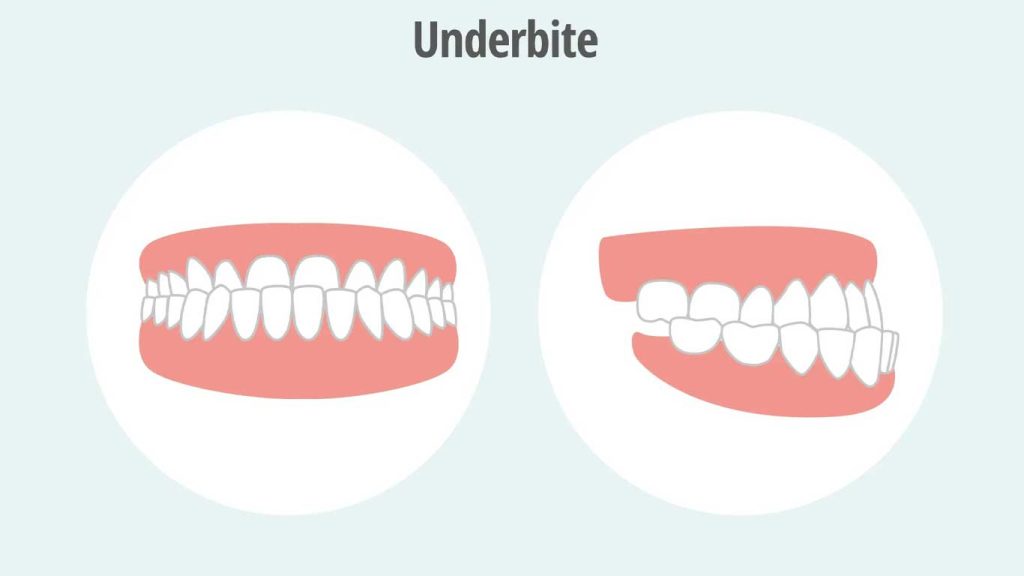

آندربایت (Underbite)، که در اصطلاح پزشکی به آن پروگناتیسم فکی (Mandibular Prognathism) نیز گفته می شود، یک نوع ناهنجاری ارتودنسی است که در آن دندان های فک پایین، هنگام بستن دهان، جلوتر از دندان های فک بالا قرار می گیرند. این وضعیت می تواند از خفیف تا شدید متغیر باشد و نه تنها بر زیبایی لبخند، بلکه بر عملکرد جویدن، صحبت کردن و حتی سلامت کلی دهان و دندان نیز تأثیر بگذارد. درک این ناهنجاری و روش های درمانی آن برای دستیابی به سلامت دهان و دندان و بهبود کیفیت زندگی بسیار مهم است. شکل صحیح قرار گرفتن دندان ها روی هم که به آن «اُکلوژن» می گویند، نقش بسیار مهمی در سلامت فک و زیبایی لبخند دارد.

همانطور که گفته شد، پروگناتیسم فکی حالتی است که در آن دندان های فک پایین جلوتر از دندان های فک بالا قرار می گیرند. این وضعیت می تواند به اشکال مختلفی بروز کند: